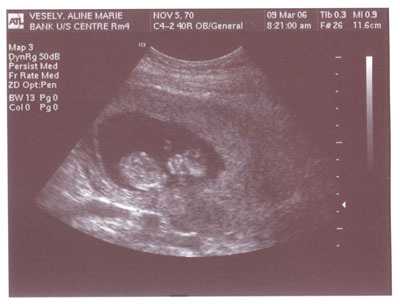

Ultrasound #1

Wow! It ain’t no joke. We’re really having a baby and now we have the photos to prove it. Aline and I had the first ultrasound today and the good news is the little grape is now the size of a baby carrot measuring 6.6 cm long. Ultrasound technician says …